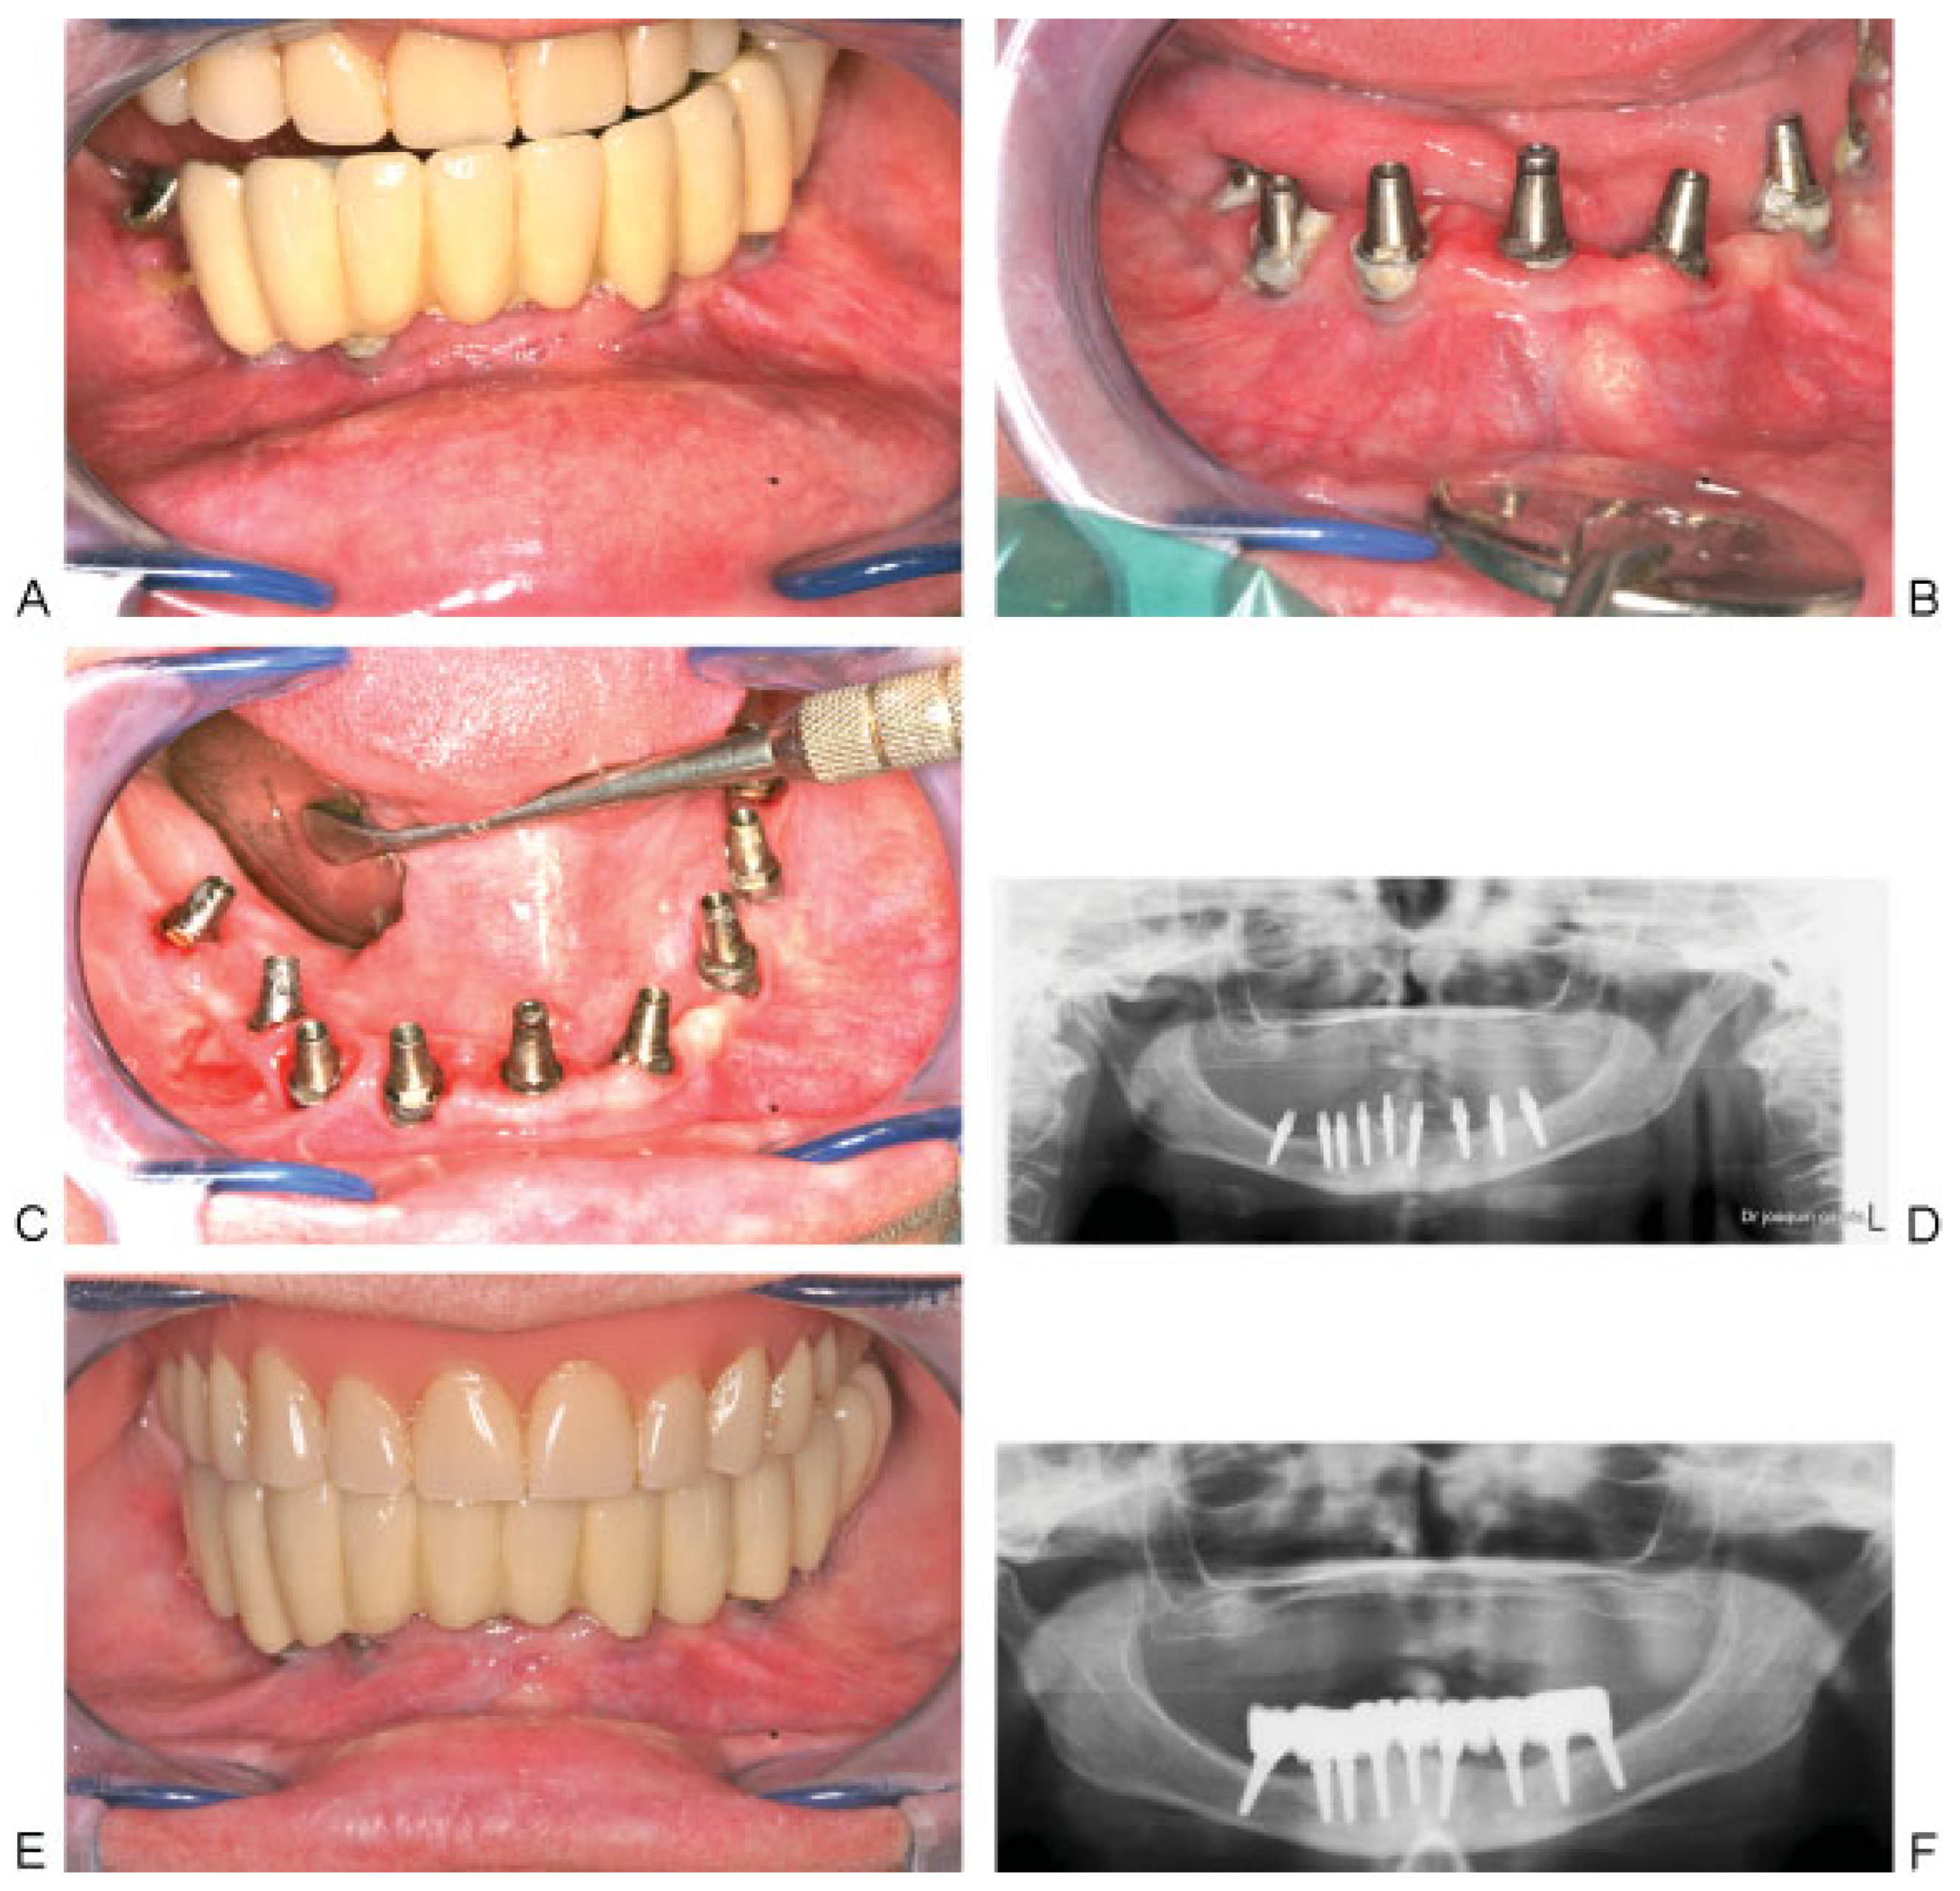

Figure 7. (A and B) Prosthesis and implants after 10 years showing accumulation of plaque and gingival inflammation. (C) Ultrasonic cleaning of implants. (D) 10 years follow-up orthopantomogram showing minimal bone resorption around implants compared with the immediate postoperative radiograph. (E) Screwing back the prosthesis. (F) Orthopantomogram after screwing and cementing back the prosthesis.

The patient after receiving the final prosthesis did not show up for any of her scheduled appointments. She returned after 10 years complaining of looseness of the prosthesis on the right side (cement-retained prosthesis). We removed the prosthesis completely to check for implant mobility and examine the gingival state.

All implants were completely osseointegrated without any signs of mobility. In three implants, one thread was observed supragingival and one implant showed two threads, without affecting the osseointegration. A low-grade gingival inflammation was observed in some parts, which was due to plaque accumulation on the undersurface of the prosthesis. Ultrasonic cleansing of the prosthesis and the implants was performed and the prosthesis was screw-retained prosthesis in place and the right part was cemented (Figure 7).